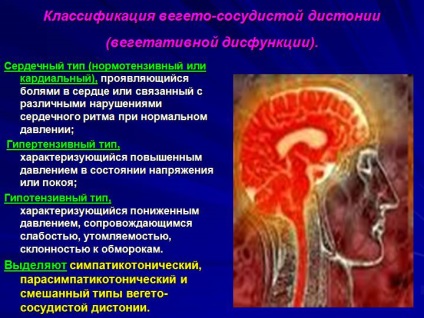

A magas vérnyomás - szükség tartalmazó termékek magnéziumsókat hajdina, zab, búza gabonafélék, dió, szójabab, bab, répa, csipkebogyó. Változások eredő hibák a menedzsment a hang a szimpatikus és a paraszimpatikus rendszer (kapcsolódó autonóm idegrendszer) a magasabb vegetatív központok kialakulásához vezet az úgynevezett vegetatív dystonia.

Ezzel szemben a szindróma, ebben a formában nem áll kapcsolatban a etiotropic tényezők és annak fejlődését jobban elősegíti a veleszületett kisebbrendűségi az SPA. Szívtípus - panaszok a szívdobogás, zavarok a szívben, néha az az érzésem, nem a levegő, lehet jelölni a szívritmus megváltozása (sinus tachycardia, súlyos légzési aritmia, supraventricularis arrhythmiák).

v) .; állapotban van, miután a hipertóniás krízis jelentős vérnyomás csökkenés (20-30% -a az eredeti szint) kíséretében gyorsan romlik a beteg egészségi állapotát; szabálytalan szívverés; fejlesztése anginás roham, súlyos gyengeség, súlyos légszomj. VVD - egy hatalmas összetett szindrómák, amelyeket az jellemez, rendellenességek a vegetatív idegrendszer, és egyéb specifikus tünetek jelezhetik nemcsak disztónia, hanem a más betegségek tüneteit nem kapcsolódó működését az idegrendszer és az agy.

Között a standard ajánlásokat lehet hallani, hogy csökkenteni kell a súlyt, a mozgást, eszik rendesen. Közben világosan meghatározott funkcionális zavarok, különösen a szív- és érrendszeri és autonóm idegrendszer, a legvilágosabban során kifejezett rohamok. Neuropszichiátriai rendellenesség aktiválásához vezet bizonyos eljárásokban, ugyanabban az időben más folyamatok lelassult, mely káros hatással van a test rendszerek, elsősorban a szív-és érrendszeri.